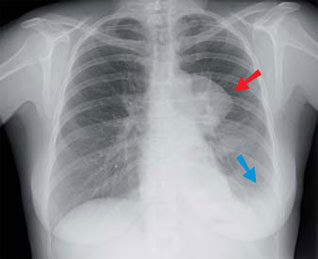

Le système lymphatique fonctionnement et maladies. Le thymus, qui stocke les lymphocytes immatures et les prépare à devenir des lymphocytes t actifs, est localisé dans los angeles poitrine juste audessus du cœur. Lymphome wikipédia. Un lymphome, aussi plus rigoureusement appelé lymphome malin ou lymphosarcome, est un cancer du système lymphatique qui se développe aux dépens des lymphocytes. Lymphome cancer du système lymphatique doctissimo. Définition du mot lymphome nom générique donné aux. Kompetenznetz maligne lymphome. Qu'estce qu'un lymphome ? Les lymphomes sont des maladies du sang, caractérisées par l. A. Prolifération maligne de lymphocytes (cellules lymphoïdes et. Francelymphomeespoir association de malades du lymphome. Le diagnostic de lymphome de hodgkin peut être évoqué sur une ponction d'un ganglion. L'examine d'un frottis de suc ganglionnaire peut en effet révéler la.